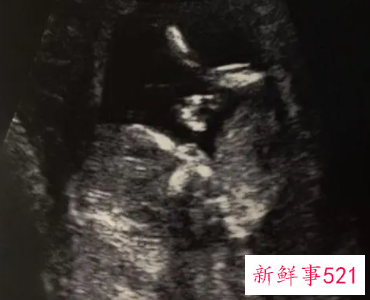

B超检查只能在妊娠5周后可以看见孕囊,妊娠6周时妊娠囊检出率达100%。妊娠6—7周可见胚芽,孕49天,胚芽径线2mm时可见原始心管搏动,妊娠8周初具人形。

第14周结束所有器官形成.,第15周结束毛发开始出现,第16周结束子宫约16CM。

第17周结束婴儿行动受限制产生胎动。第21周结束第二次扫描。第22周结束知道性别。

在女性怀孕18周到24周之间,我们也要去做排畸的三维B超检查,到32周左右也可以做二维的B超,这主要是查看宝宝的发育情况。